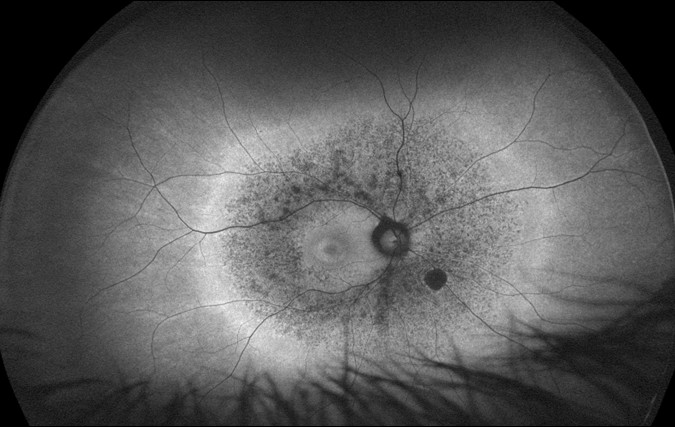

Glaucoma, Ischaemic optic neuropathy, Crowded versus Choked disc.

Macular disease, diabetic retinopathy, vascular hypertension, ocular neoplasia, vitreous and peripheral retina conditions.